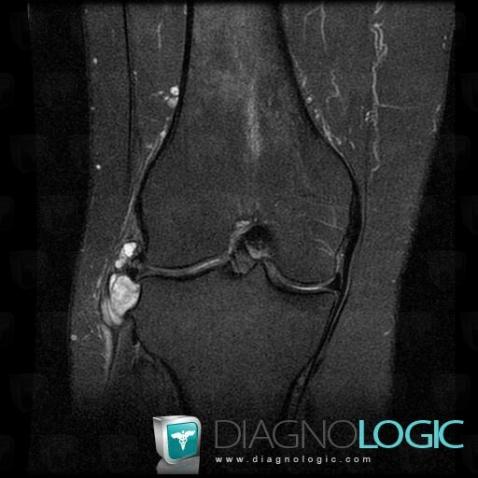

Kyste mucoïde, Autres parties molles/nerfs - Genou, IRM

Voici les informations spécifiques à l'image clé ci dessus:

- Diagnostic Kyste mucoïde, Localisation(s) Autres parties molles/nerfs - Genou, comportant les gammes Masse des parties molles juxta articulaires

- Diagnostic Kyste mucoïde (lié à Kyste mucoïde), Localisation(s) Autres parties molles/nerfs - Genou, comportant les gammes Masse kystique et pseudo kystique des parties molles